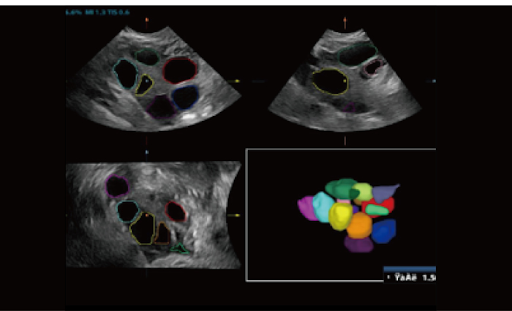

Smart FLC

Smart FLC автоматически определяет количество фолликулов и рассчитывает объем каждого из них используя 3D-данные яичника. Всё это обеспечивает точную оценку размера фолликулов, что особенно важно при ЭКО.